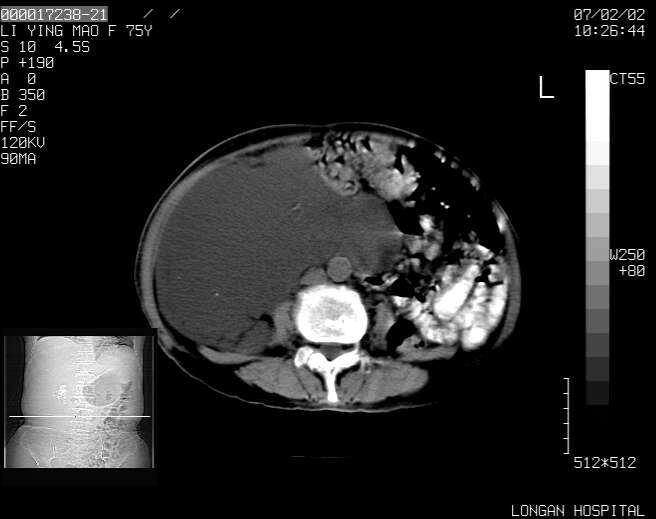

以下是引用dyqct在2007-2-10 8:53:00的发言:[br]考虑:1、肝脏多发囊肿[br] 2、左肾囊肿,右肾多发结石并积水。[br] 3、右胸少量积液。[br] 4、右肾周包裹性积液或淋巴管瘤(有见缝就钻的征象、薄隔、小结节状钙化)?[br] 5、腰椎动脉瘤样骨囊肿?[br] [br] [br]